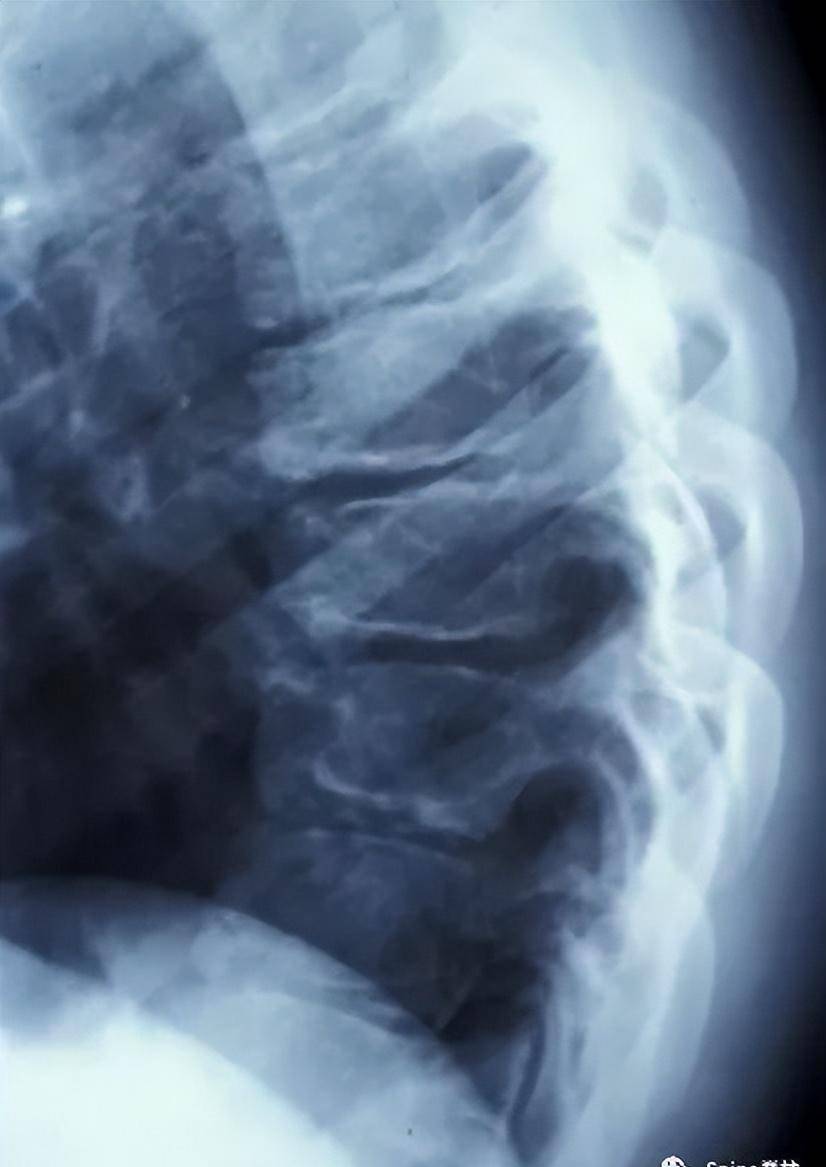

脊柱休门氏病scheuermannsdisease

图片尺寸350x294